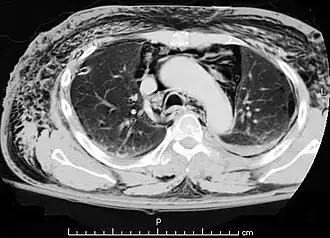

![]() Una TAC que muestra aire en el mediastino | ||

El neumomediastino se define como la presencia de aire en el mediastino observado mediante una radiografía o prueba de imagen mediante TAC.[1] Normalmente ocurre cuando el aire sale de la vía aérea, el pulmón o el esófago y entra en esta cavidad. El neumomediastino (del griego pneuma —aire—, también denominado «enfisema mediastínico»)[2] hace referencia a la neumatosis (presencia anómala de aire u otro gas) en el mediastino, la parte central de la cavidad torácica.

El diagnóstico puede confirmarse mediante una radiografía de tórax en la que aparezca un contorno radiolúcido alrededor del corazón y el mediastino o mediante un TAC de tórax.